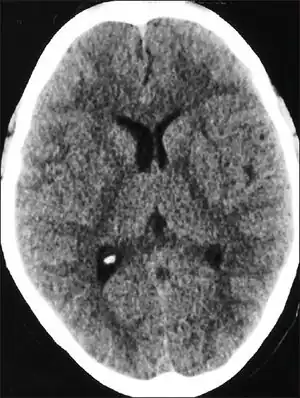

| CT scan of the head showing diffuse effacement of cerebral sulci and compression of the ventricles in a case with high altitude cerebral edema[1] | |

People with HACE have an elevated white blood cell count, but otherwise their blood count and biochemistry are normal. If a lumbar puncture is performed, it will show normal cerebral spinal fluid and cell counts but an increase in pressure.[10] In one study, CT scans of patients with HACE exhibited ventricle compression and low density in the cerebellum.[10] Only a few autopsies have been performed on fatal cases of HACE;[11] they showed swollen gyri, spongiosis of white matter, and compressed sulci. There was some variation between individuals, and the results may not be typical of HACE deaths.[11]